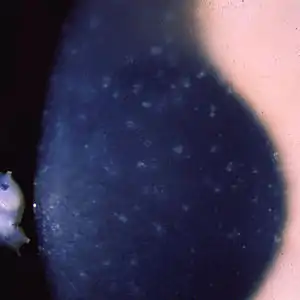

| Multiple opaque spots in the corneal epithelium | |

Patients with Meesmann corneal dystrophy may remain asymptomatic or experience mild symptoms. Symptoms of Meesmann corneal dystrophy often go unnoticed and is usually found and diagnosed during routine eye examinations.[13] This slowly progressive disorder is characterized by microcysts that are filled with debris in the epithelium of the cornea detected and clinically diagnosed with slit-lamp biomicroscopy and retroillumination.[1][9] Under electron microscopy, there are an abnormal aggregation of keratin filament bundles in the center of the cornea.[12] It was found to not affect the corneal stromal layer or endothelial cell layer.[14] Signs of this disease appear in the early first few years of life and begin as eye irritation. Under magnification, corneal changes consisting of punctate opacities in the epithelium are found. Occasionally, these are found in the Bowman membrane. Patients diagnosed with Meesmann corneal dystrophy are unable to tolerate the use of contact lenses which irritate the corneal epithelium. Light microscopy and electron microscopy found that the basement membrane is thickened with an intracytoplasmic substance. Under slit-lamp photography, the cornea was found to be uneven due to the damage and scarring from the thickening basement membrane and anterior stroma. The buildup of foreign materials may cause vision blurriness or cloudiness.[6]